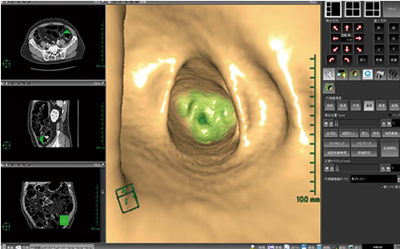

9. マルチボリューム内視鏡

“マルチボリューム内視鏡”は,ボリュームデータを視野角を持った画像として観察できる内視鏡ソフトウェアに,異なるシリーズのボリュームデータをまとめて表示できるマルチボリューム機能が付加されたソフトウェアである。このソフトウェアにより,SPECTによる機能画像とCTによる形態画像

を仮想内視鏡画像として同時に表示,観察することで,腹腔鏡,縦隔鏡,胸腔鏡のシミュレーションのサポートなどに有用である。また,大腸仮想内視鏡像と別データで取得したポリープやアップルコアなどの情報も同時に表示可能である(図11)。

図11 マルチボリューム内視鏡